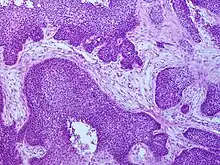

_squamous_cell_carcinoma_histopathology.jpg.webp)

Medical history, physical examination and medical imaging may suggest a squamous-cell carcinoma, but a biopsy for histopathology generally establishes the diagnosis. TP63 staining is the main histological marker for squamous-cell carcinoma. In addition, TP63 is an essential transcription factor to establish identity of the squamous cells.[16]